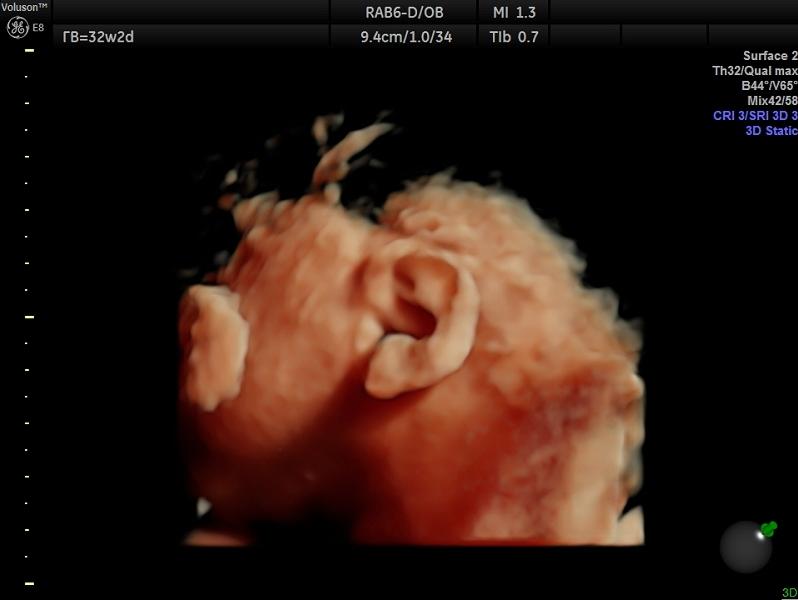

Сегодня сходили на наше третье скрининговое УЗИ и кажись под конец беременности меня срубило, посыпалась, когда показали его ушко и оно оказалось очень похожим на ухо мужа 🤣 Ёмоё, я не думала, что буду плакать. С малышом и мной все хорошо. Единственное - опережает на неделю, врач сказал, что есть вероятность родить крупный плод, а у меня все мимо ушей проплывало, потому что сын в правильном положении в первый раз за все УЗИ, щекастый, со своим особенным характером уже в утробе 😱 Все утро пересм...